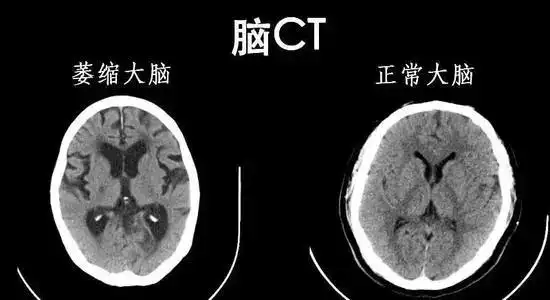

脑萎缩原本是在ct或mri检查时,发现脑组织体积减小和脑室扩大等而命名